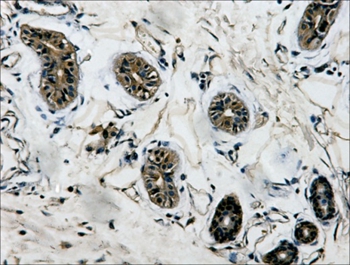

图片:

IHC staining of Human colon tissue with β-tubulin mouse mAb(5G3) diluted at 1:200.